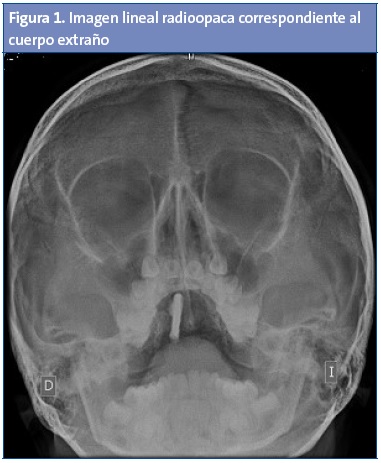

Se realiza radiografía de Waters (Fig. 1), en donde se observa un edema leve de la mucosa del seno maxilar derecho, compatible con sinusitis derecha leve. En paladar duro existe una imagen lineal radioopaca.

Tras ello es remitida a Otorrinolaringología, donde se le realiza una rinoscopia anterior, encontrando un cuerpo extraño en la fosa nasal derecha (una moneda de 5 céntimos). Tras la retirada del mismo presenta resolución espontánea de la rinorrea en pocos días.